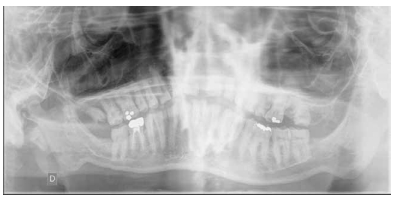

En la bibliografía se describe con detalle los defectos del esmalte que presentan los pacientes diagnosticados del síndrome de Morquio. Estos defectos son una característica aparentemente constante en la enfermedad y, por lo tanto, hace necesaria las visitas al odontólogo para su control evitándose problemas mayores. Dichos defectos consisten en un esmalte anormalmente delgado, que es áspero debido a los numerosos hoyos diminutos y a una superficie irregular. La delgadez del esmalte da como resultado una forma alterada y decoloración de los dientes que, añadido a los diastemas interdentales, provocan alteraciones en la oclusión. Aparte de estos defectos, el esmalte es histológicamente normal y tiene una dureza y radiodensidad normales. El tratamiento odontológico de los pacientes con MPS-IV requiere colaboración multidisciplinar, debido a que las manifestaciones orales de la enfermedad pueden aparecer a cualquier edad, resultando en ocasiones tedioso para el paciente y complicado para el profesional. Especial mención merecen las terapias utilizadas como tratamiento sintomático de la enfermedad, así como el manejo de la vía aérea en el caso de intervenciones bajo anestesia general o sedación para tratar ciertas patologías del territorio bucomaxilodental.

The enamel defects presented by patients diagnosed with Morquio syndrome are described in detail in the bibliography. These defects are an apparently constant feature in the disease and, therefore, make visits to the dentist necessary for their control, avoiding major problems. These defects consist of an abnormally thin enamel that is rough due to numerous tiny holes and an irregular surface. The thinness of the enamel results in an altered form and discoloration of the teeth, which added to the interdental diastemas, cause alterations in the occlusion. Apart from these defects, the enamel is histologically normal and has a normal hardness and radiodensity.

Dental treatment of patients with MPS-IV requires multidisciplinary collaboration, because the oral manifestations of the disease can appear at any age, being sometimes tedious for the patient and complicated for the professional. Special mention should be made of the therapies used as a symptomatic treatment of the disease, as well as the management of the airway in the case of interventions under general anesthesia or sedation to treat certain pathologies of the bucomaxillodental territory.